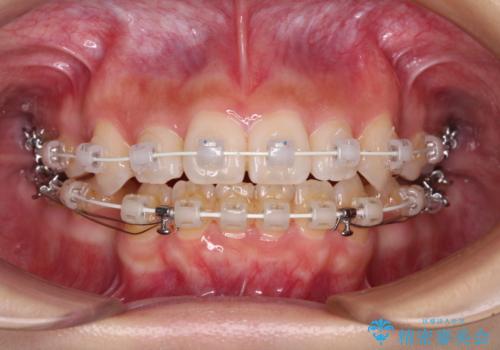

- 矯正装置

- 審美装置

- 上下前歯のデコボコと八重歯を気にして来院された患者様です。

叢生を解消する際に出っ歯とならないようにするために、上下左右の小臼歯計4本を抜歯することとしました。

奥歯の咬み合わせが理想的であり、歯の移動に時間のかかる出っ歯でもなかったため、2年程度で治療を終えることを目標としましたが、無事に予定通りの2年間で終えることができました。